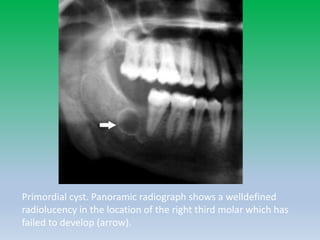

Primordial Cyst

• A less common cystic lesion is the primordial

cyst, which develops instead of a tooth.

• It is believed that the dental follicle forms but

subsequently undergoes cystic degeneration

before completion of odontogenesis.

• The non expansile lesion is well defined and

radiolucent, without an associated tooth.

Primordial cyst. Panoramic radiograph shows a welldefined

radiolucency in the location of the right third molar which has

failed to develop (arrow).